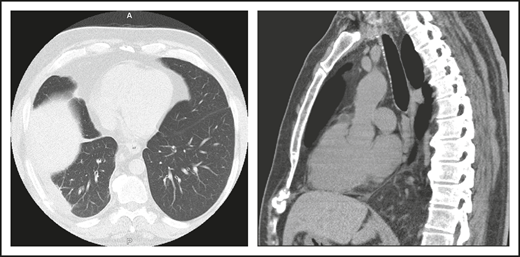

A second common reason for a patient to come to the attention of hematologists is the finding of an enlarged spleen, especially in an adult with lymphadenopathy. This was the reason in patient 2, who is now a 46-year-old male professional dog walker. At the age of 31, he was found to have an enlarged spleen together with cervical and axillary lymphadenopathy. Hematology was consulted, and the lymph node was biopsied; pathology revealed that he had noncaseating granuloma. He was then referred to pulmonology and, with this evidence, was diagnosed with sarcoidosis and treated with steroids for some months, but he stopped the treatment. Although he had no obvious respiratory symptoms over the following 15 years, he had a slow decline in lung function, and chest computed tomography showed hilar lymphadenopathy, ground-glass opacities with nodules, and bronchiectatic changes (Figure 2). In 2018, he had acute bacterial pneumonia, became concerned, and found on the internet that granulomata in the lungs and an enlarged spleen might be related to low serum immunoglobulin levels. He asked that this be tested; when this test was performed, he had striking low serum immunoglobulins: IgG, 97 mg/dL; IgA, <5 mg/dL; IgM, 27 mg/dL. However, within the month, he was hospitalized for pneumonia due to metapneumovirus. The diagnosis of CVID was finally made, and immunoglobulin treatment was started. The patient’s spleen remains large.

The patient in clinical case 2 had a slow decline in lung function due to his immune defect, but this was assumed to be due to sarcoidosis. Chest computed tomography showed ground-glass opacities with numerous nodules, hilar lymphadenopathy, and bronchiectatic changes. With granuloma on biopsy, these changes were consistent with granulomatous lymphocytic interstitial lung disease.